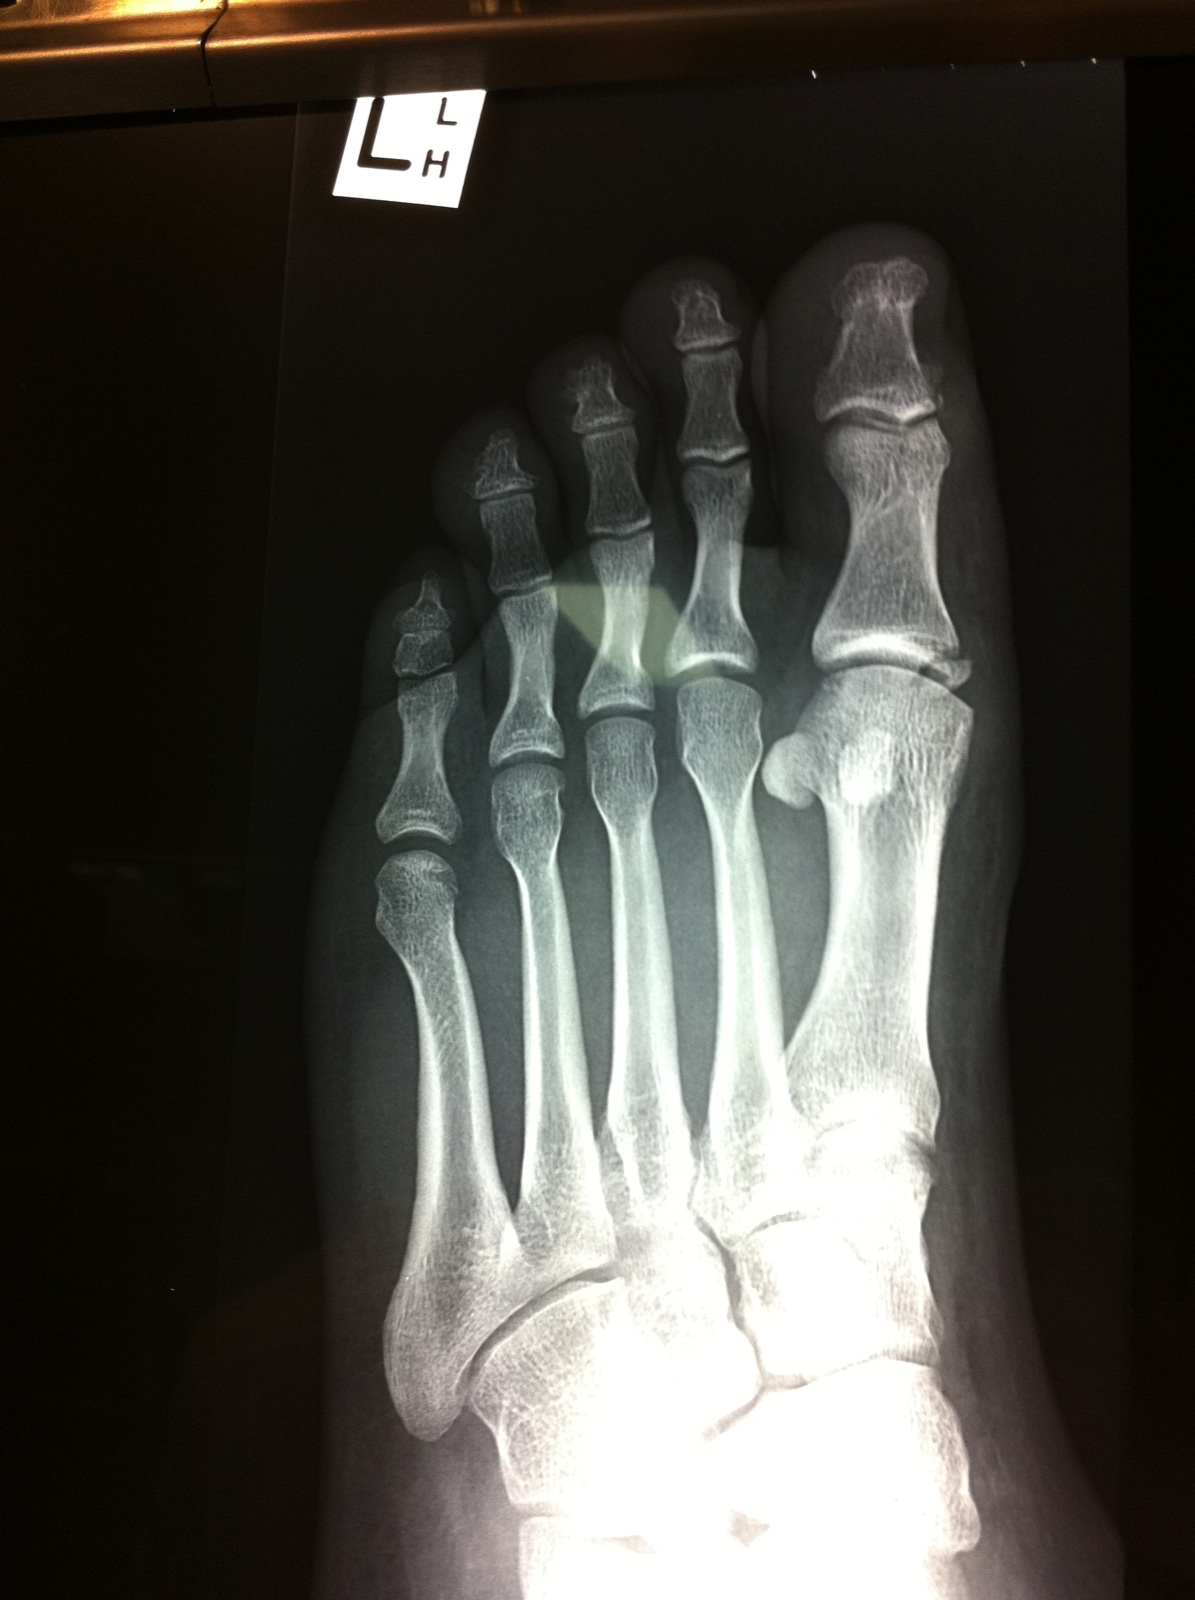

Just been to docs, and i have a brken big toe. with a chunk of bone floating. Pin/screw or Not will be 4-6 weeks in cast